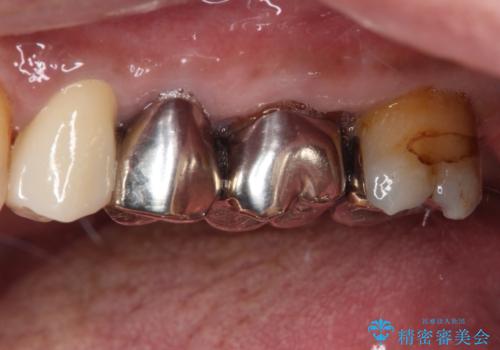

- 詰め物が欠けてしまい、虫歯かもしれないから診てほしいとのことで来院された患者様です。

精査の結果、詰め物の下に虫歯が大きく広がっているのがわかりました。

虫歯の範囲が大きく、部分的な詰め物では対応が難しいため、オールセラミッククラウンにて補綴することとしました。

外見からはあまり大きな虫歯があるようには見えなくても、X線検査をすることで、詰め物の下に虫歯が広がっていることは多々あります。

定期的に歯科医院を受診し、早期発見・早期治療をすることで、歯の神経を残す治療が可能になります。